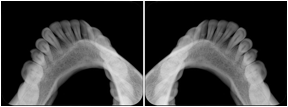

Cephalometric Series Structured Display

Figure OO-2. Cephalometric Series Structured Display